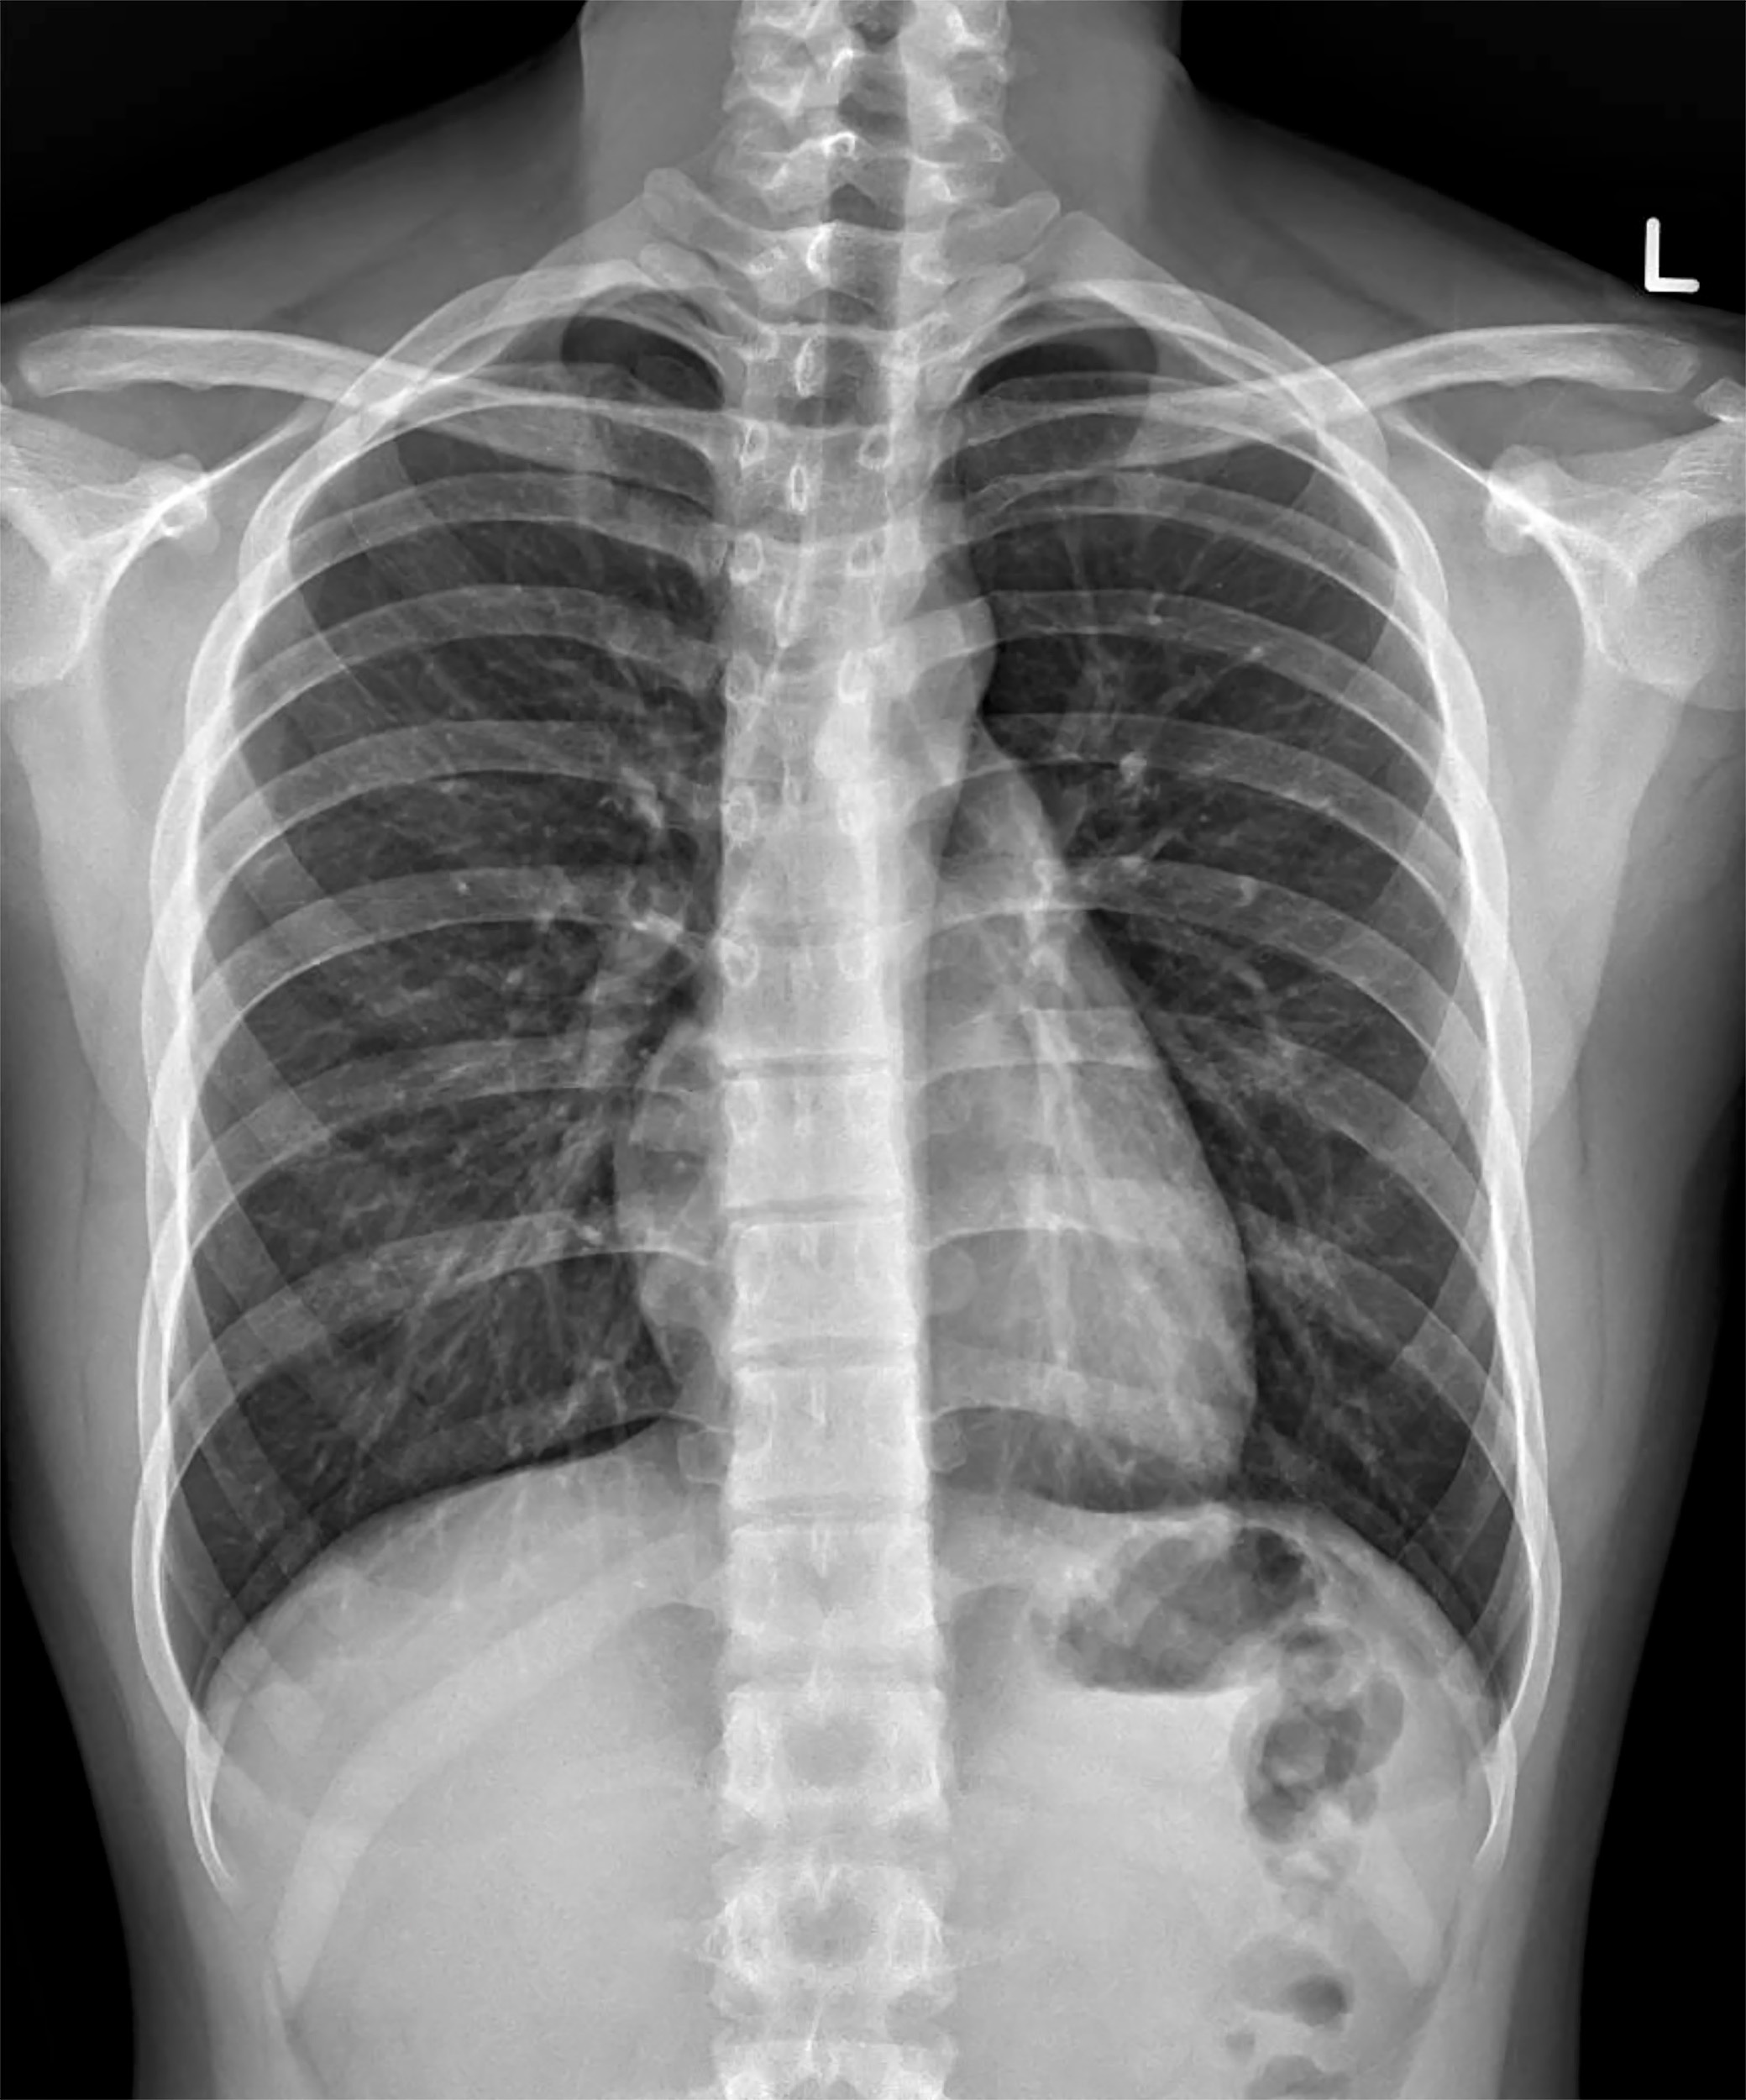

Dysplastic glenoid tubercle predisposing patient to recurrent dislocations.All figures courtesy of Dr. Graeme Abreu, Royal Brisbane and Women’s Hospital, and presented at RANZCR 2025 ASM.